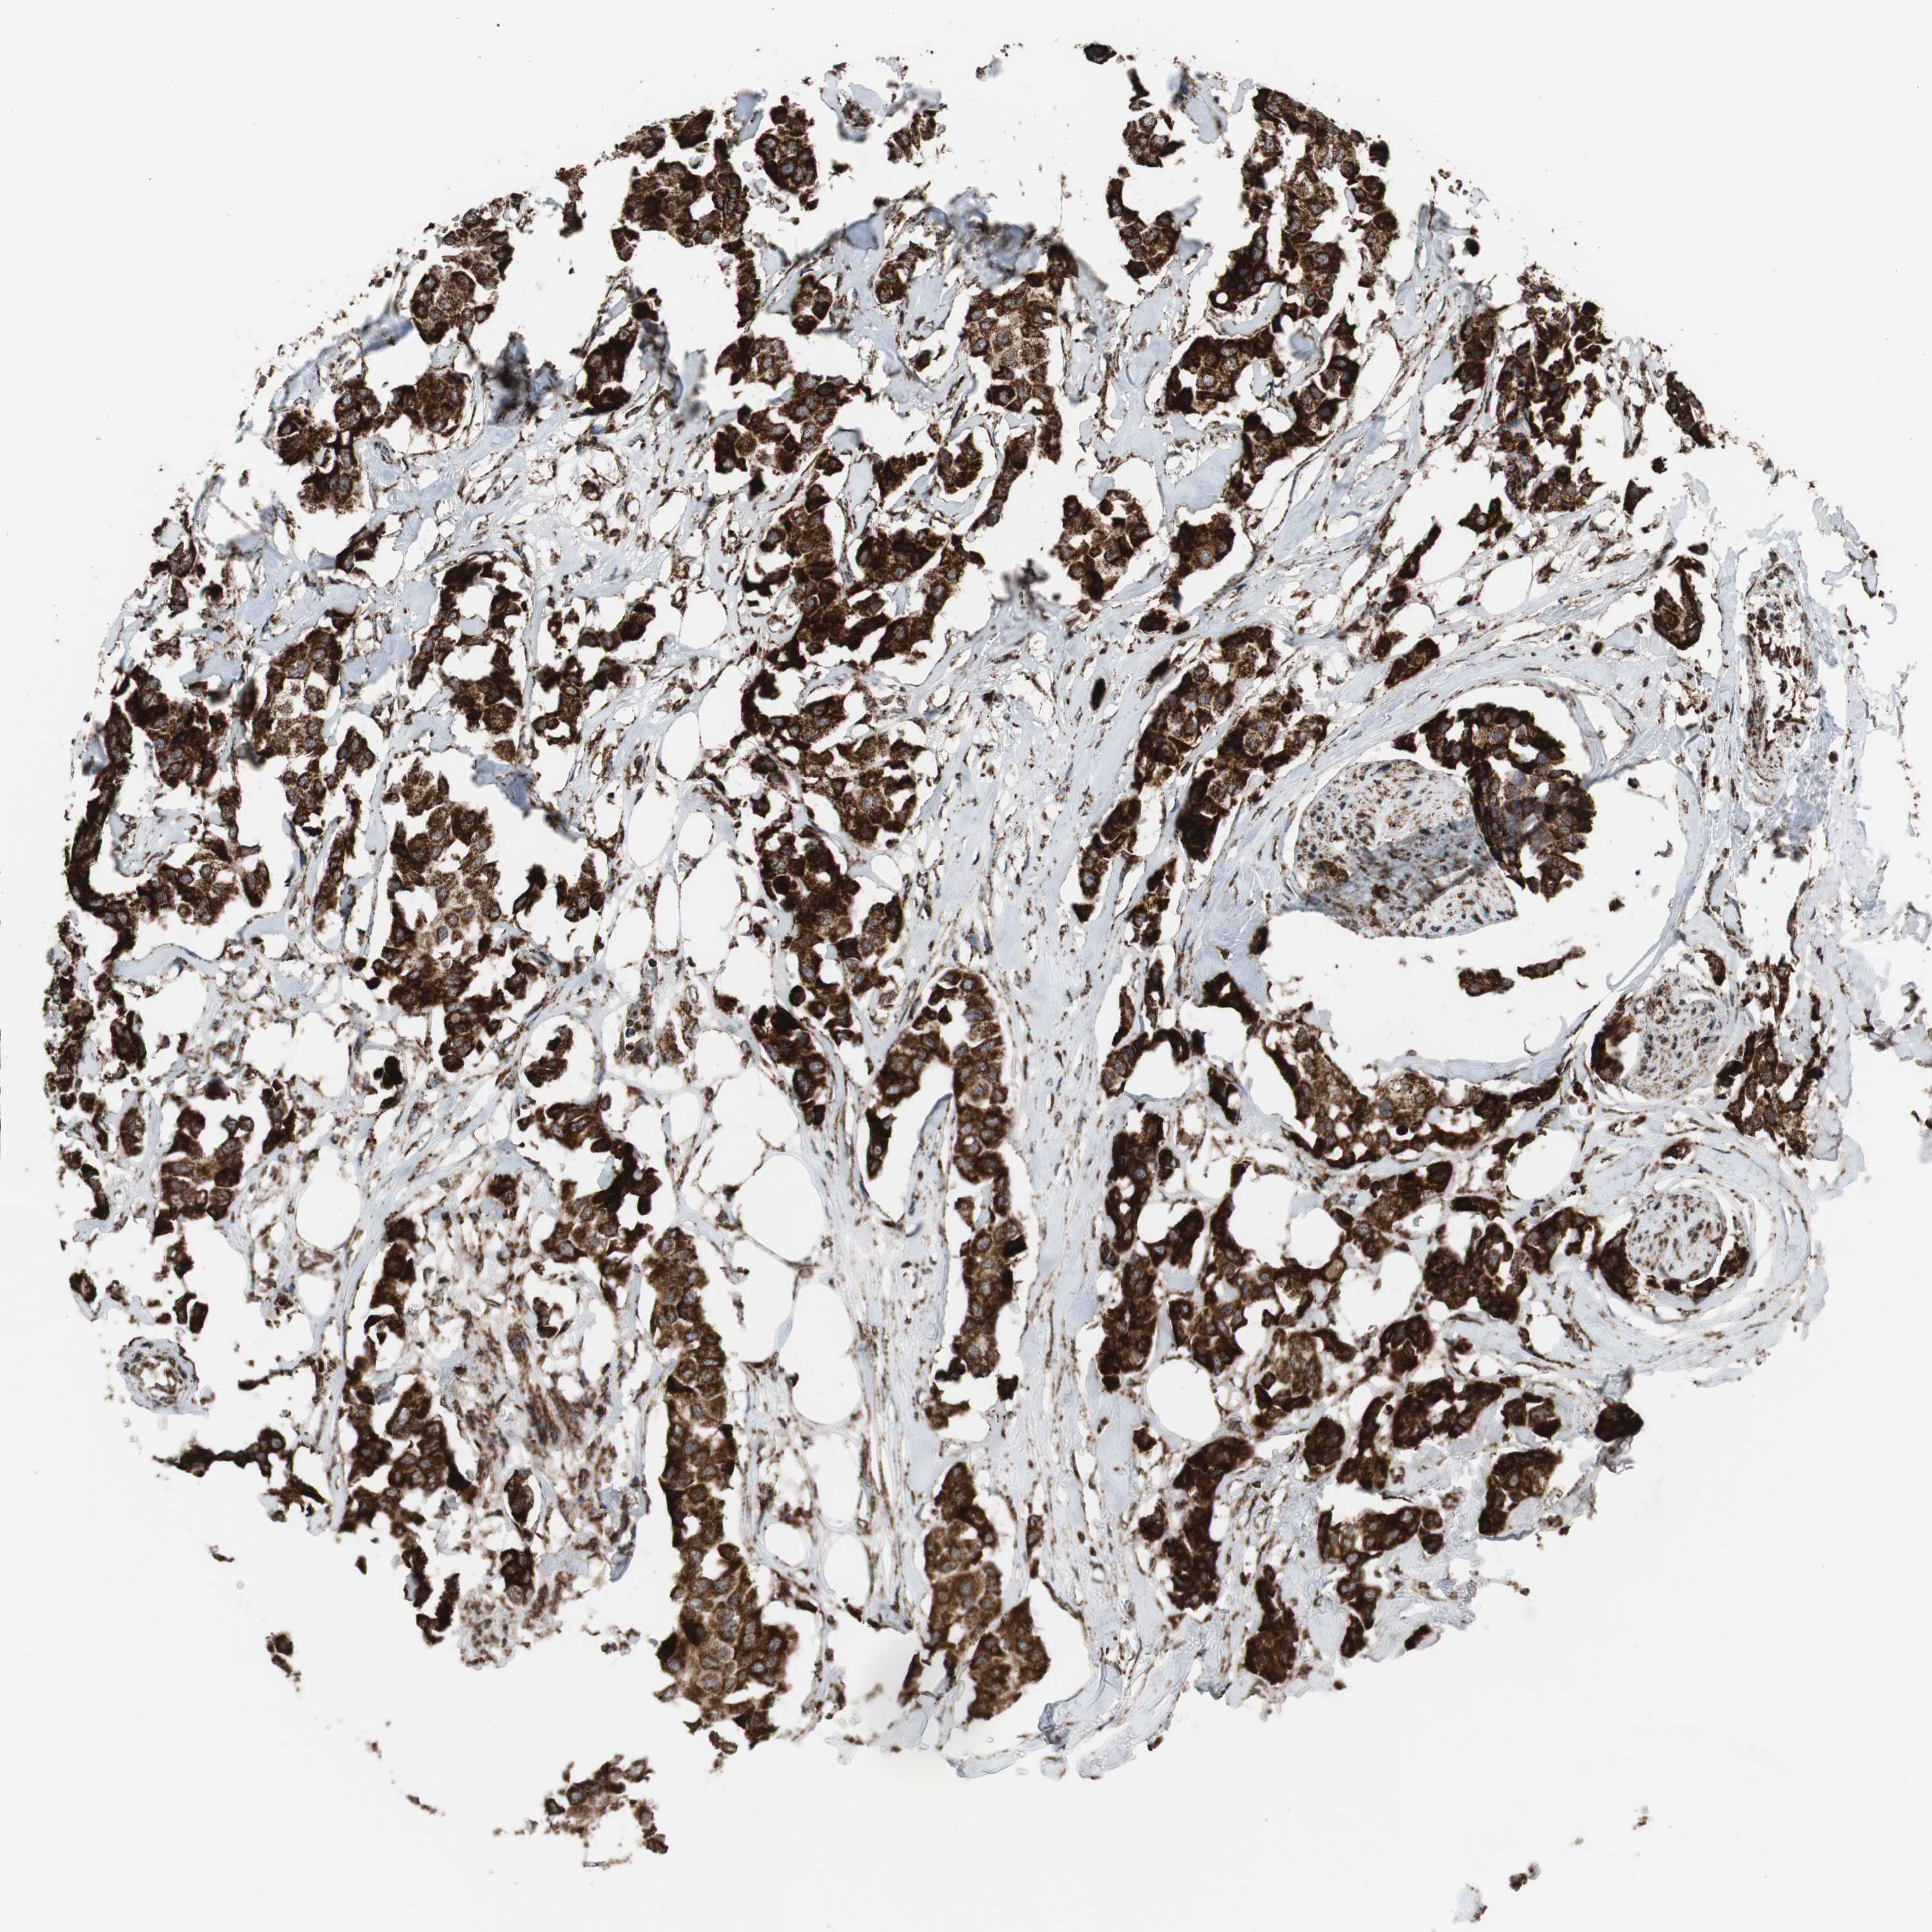

CANCER BREAST CANCER Show tissue menu

BRCA TCGA BRCA VALIDATION PROTEIN EXPRESSION